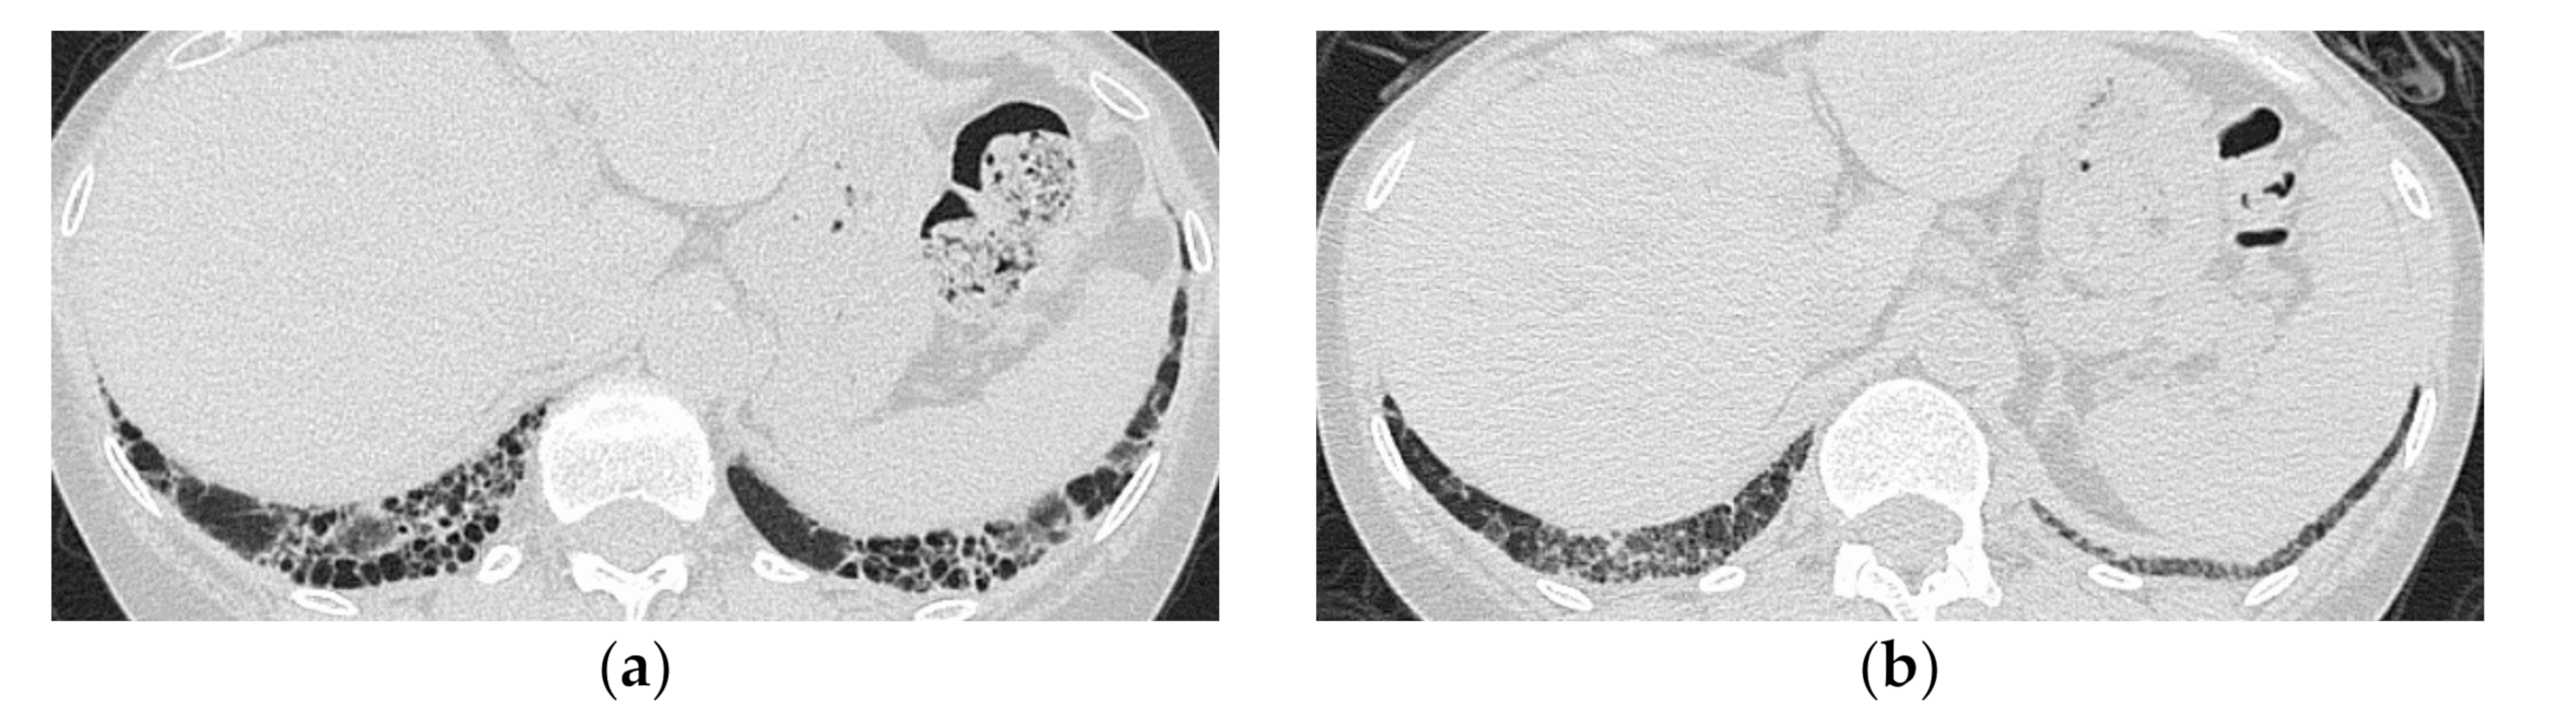

3.1. Anti-Aminoacyl tRNA Synthetase Antibody (Anti-ARS Ab)

HRCT Findings of Patients with Anti-ARS Ab